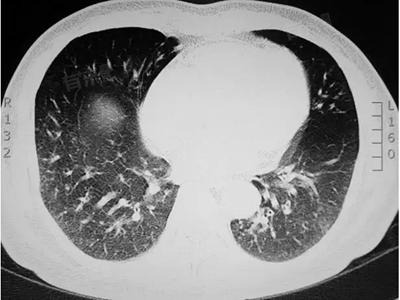

肺部有空洞是多种肺部疾病的共同影像学特征,包括肺结核、肺脓肿、肺霉菌病等,建议及时就医检查确诊,并在专业医生的指导下进行治疗。

2、肺结核:肺结核是导致肺部空洞的常见感染性疾病,结核杆菌感染肺部组织,导致局部坏死和液化,形成空洞。肺结核患者常伴有咳嗽、咳痰、低热、胸闷等症状。

3、肺霉菌病:肺霉菌病是肺部真菌感染引起的疾病,霉菌侵袭肺部组织,造成损伤,引发空洞,病情可能较为严重。

5、肺癌:肺癌是导致肺部空洞的最严重疾病,肿瘤细胞破坏肺组织,形成空洞,肺癌患者多表现为咳嗽、咯血,部分因空洞感染可伴有发热。